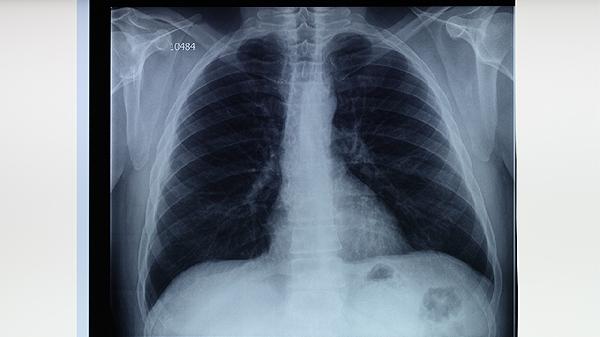

肺结核主要是靠呼吸道和通过飞沫传播的,比如通过病人咳嗽打喷嚏这些传播。当然通过皮肤、消化道、胎盘也可以传播,但是这种传播途径比较罕见。预防第一是要及早发现、注意隔离、减少传播,第二是要注意加强锻炼、劳逸结合,要经常开窗通风,另外接种卡介疫苗也可以预防肺结核。